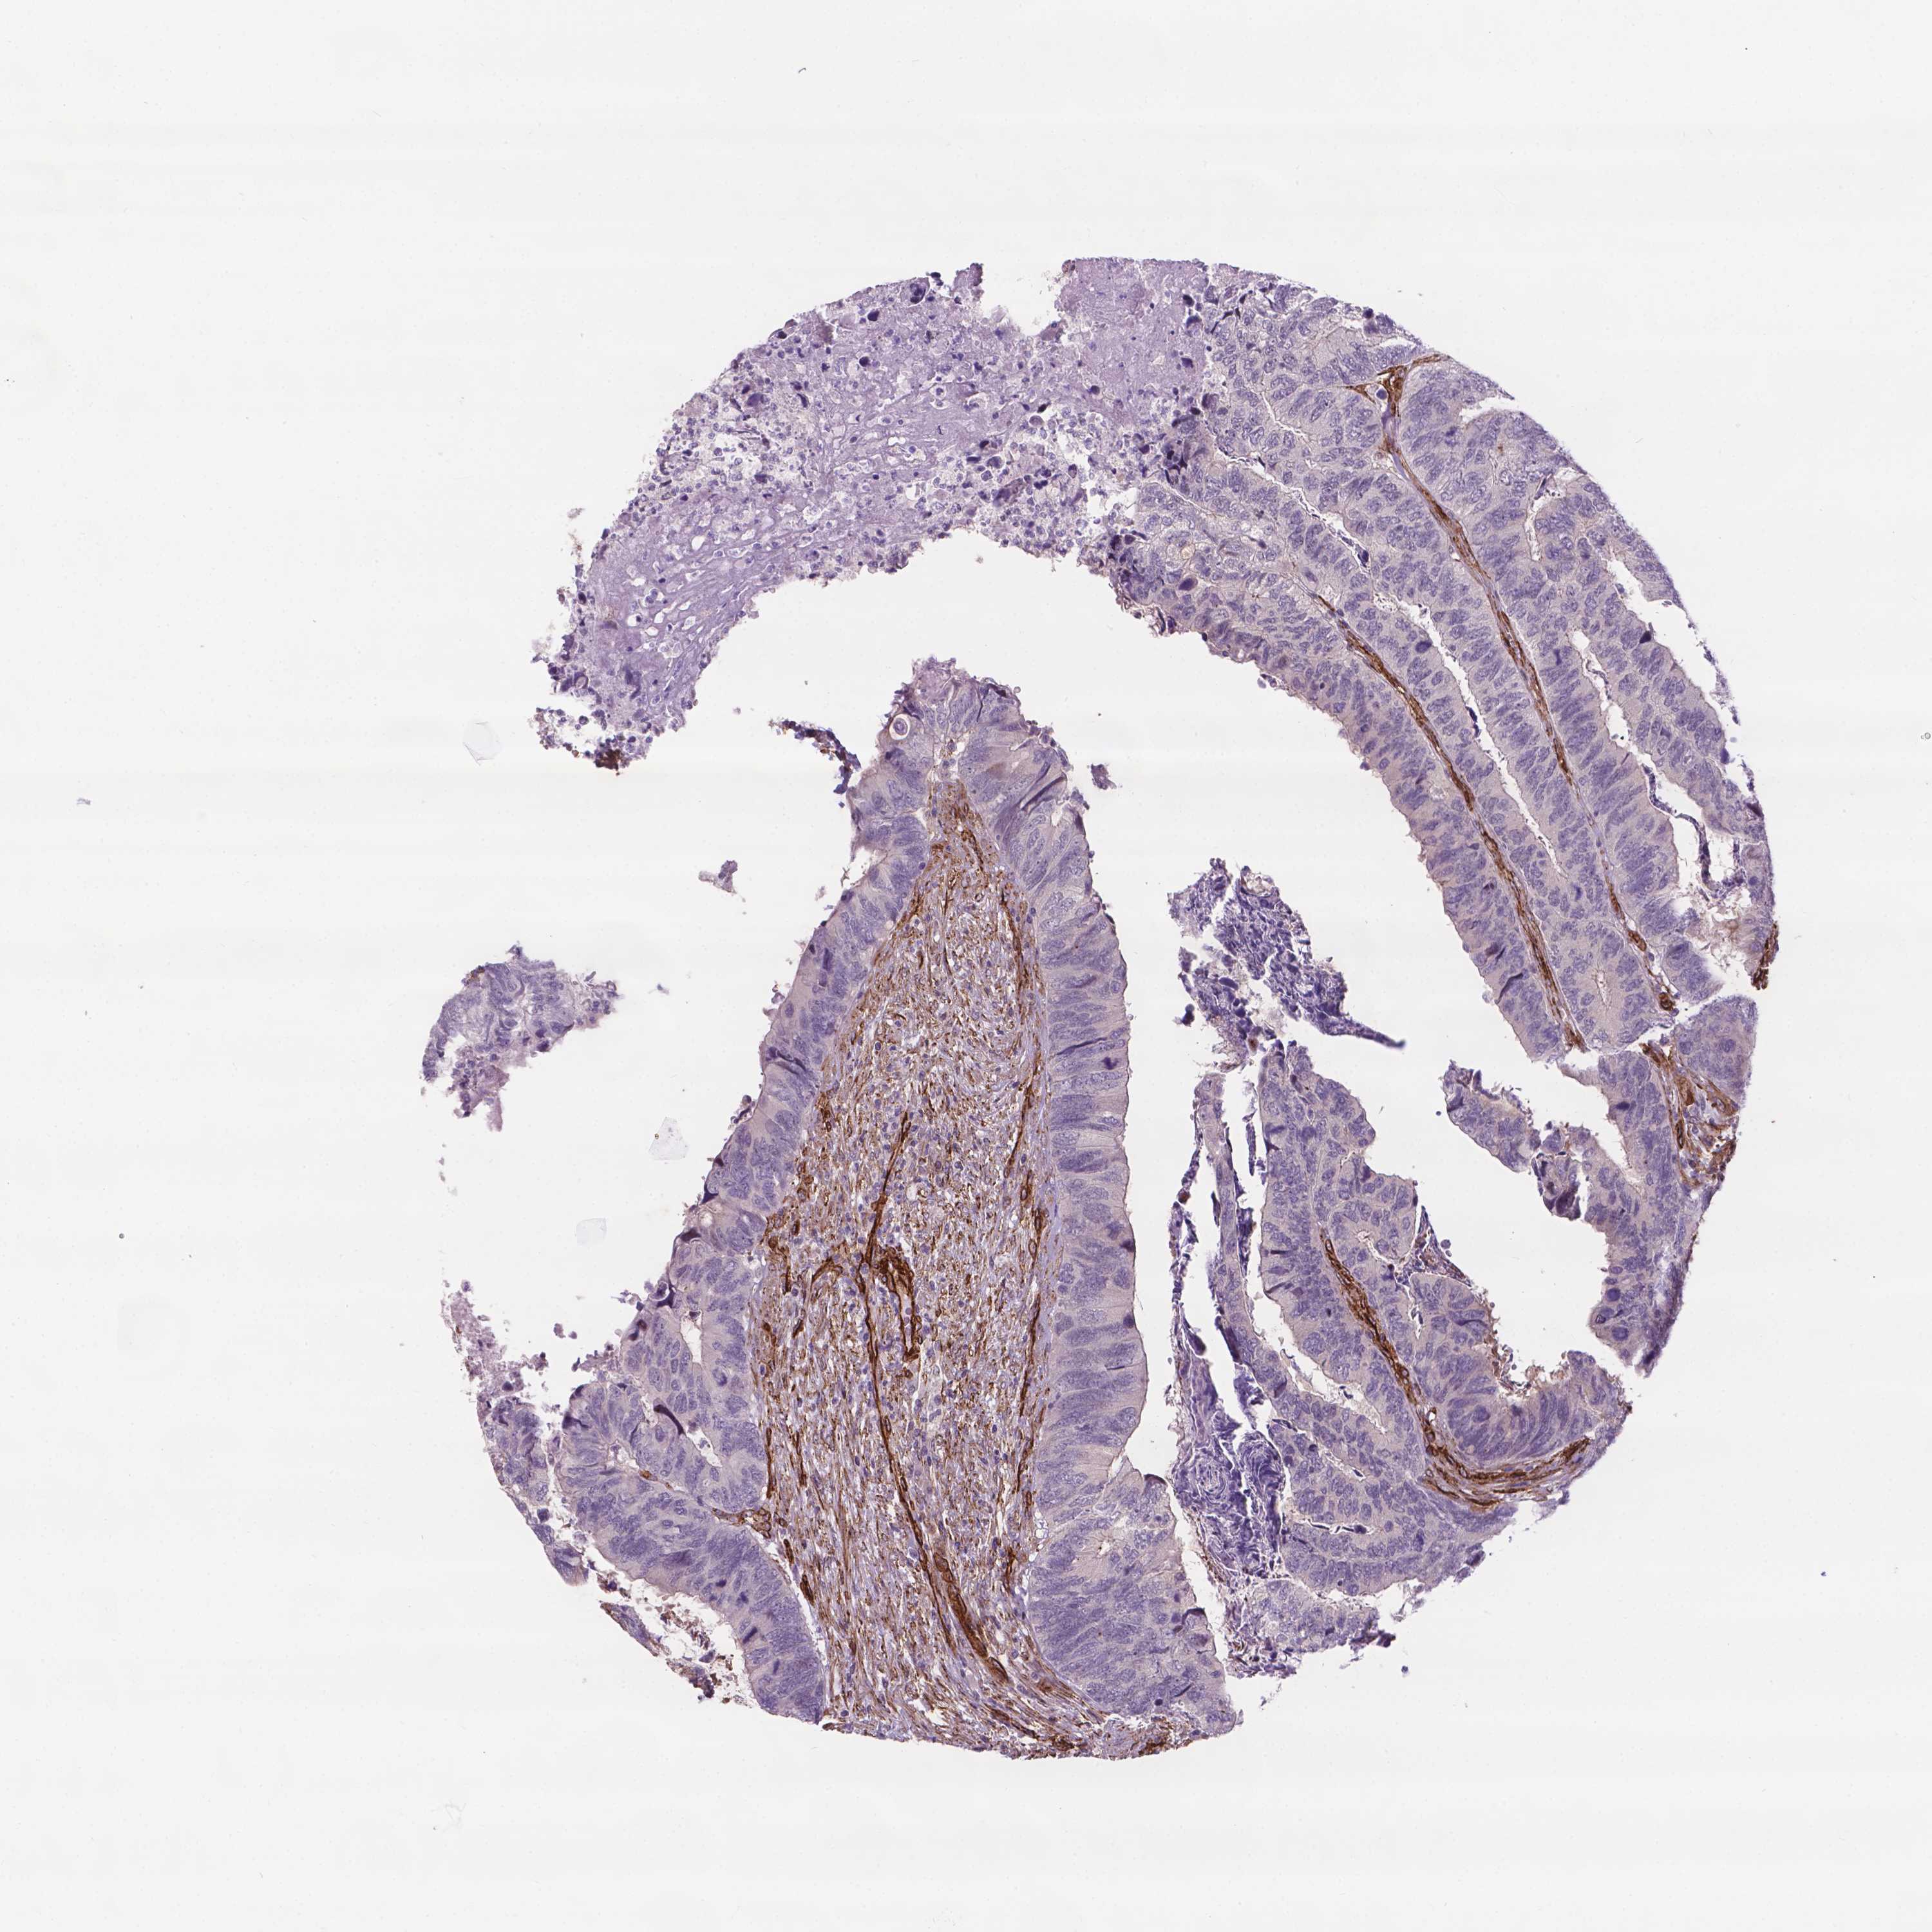

CANCER COLORECTAL CANCER Show tissue menu

Colorectal cancer

Human cancer